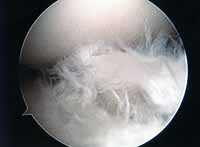

(水平断裂合併)

(水平断裂は僅かに残存)

正常に見えるが